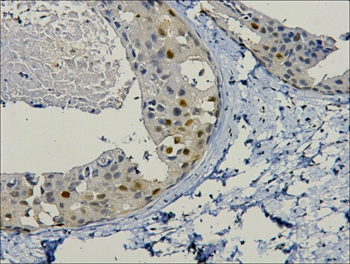

IHC staining of paraffin- embedded Human breast cancer tissue with PCNA mouse mAb (12D10) diluted at 1:200.

Immunohistochemistry: 1:200